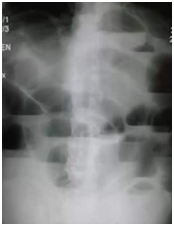

西医答辩例题1:【临床判读】根据下面X线片判断临床意义。(5分)

【正确答案】 参考答题要点:单纯性小肠梗阻。

单纯性小肠梗阻是小肠内容物运行障碍所致的急腹症。典型临床表现为腹痛、腹胀、呕吐。腹部立位片显示腹腔内多发阶梯状气液平面。

【该题针对“X线片”知识点进行考核】